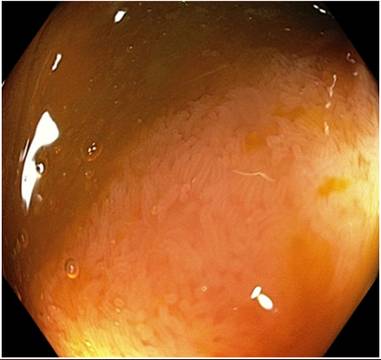

Колоноскопия от 11.2017 г – неизлекуван участък

Колоноскопия от 12.04.2018 г – неизлекуван участък

Особено впечатление направиха множеството допълнително появили се белезникави налепи и то при положение, че хиперемията както и оточността са леко намалени.

Тези налепи се оказаха и проблемът, все още този останал малък участък да не е напълно възстановен и регенериран, както и да провокира състояния, некорелиращи с общото много добро състояние на останалата – над 90% здрава чревна система. Тук трябва да споменем, че поради именно тези некорелиращи състояния, може да се допускат грешки при воденето на основните, базови терапии, в смисъл, да се водят намаляващи или обратното – увеличаващи дозите на препаратите интервенции. Това изрично споменаваме, за да се види значимостта на контролните колоноскопии.

За нас, тези налепи са с комбинирано полипоиден, но и бактериален характер и за това, спешно бе модифициран промивния агент по ЗРХТ – АТС 105. Тук е мястото да споменем, че високият професионализъм и нетърпящите съмнения високи умения на водилия колоноскопията – позволяваме си да го назовем – д-р Драганов, бяха изключително важни, за да сме уверени в правилността на посоката ни към модифициране на промивния препарат АТС 105. При по силен допир, тези налепи отпадат и оставят на мястото си кървящ участък. Веднага бе предписана орална антибактериална терапия, а ние формирахме нова по вид, целева промивно-контактна терапия с промивния АТС 105 и нов вид анален крем. Не може да не опишем и един периодично проявявал се проблем при Т.П. – оточност и нереагиране (за волева контракция) на ануса, при което се създава сериозен проблем със задържането (включително и на промивките). В момента на колоноскопията – отново е активен.